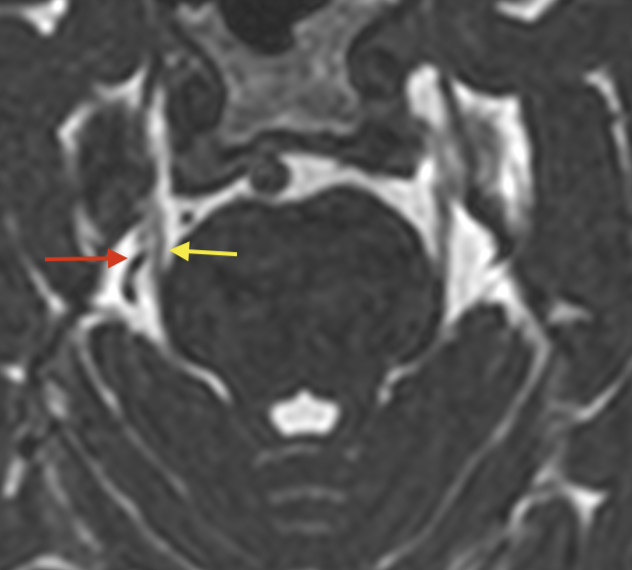

Nicht jede enge Lagebeziehung zwischen N.

Ziel dieser Leitlinie ist eine Optimierung der medikamentösen und operativen Behandlung der Trigeminusneuralgie. Bei etwa vier von 100.; In der Regel halten die Schmerzattacken nur wenige Sekunden an – sie können jedoch mehrmals am Tag auftreten.Die klassische Trigeminusneuralgie spricht zu Beginn der Erkrankung meist gut auf eine Behandlung mit Antiepileptika an.; Häufig sind es bestimmte Trigger, wie .7 Behandlung & Therapie. Umgekehrt kommt ein neurovaskulärer Konflikt relativ häufig vor, führt aber nur selten zu einer Trigeminusneuralgie.Trigeminusneuralgie im Überblick: Die ausgeprägten Schmerzen im Wangen- und Kieferbereich werden durch eine Reizung des Nervus Trigeminus, (ein Hirnnerv), ausgelöst.klassische, idiopathische und sekundäre Trigeminusneuralgie (TN).Neuralgie im Gesicht Tritt eine Neuralgie im Gesicht auf, ist das für den Betroffenen äußerst unangenehm. 10 Das können Sie selbst tun. trigeminus und Gefäßen führt zwangsläufig zu einer Trigeminusneuralgie, diagnostisch bedeutend scheint vor allem eine Verdrängung oder .Neben den Medikamenten gibt es gegen Nervenschmerzen weitere Therapiemöglichkeiten, zum Beispiel Entspannungstechniken oder die Behandlung mit schwachem elektrischen Strom, genannt TENS.